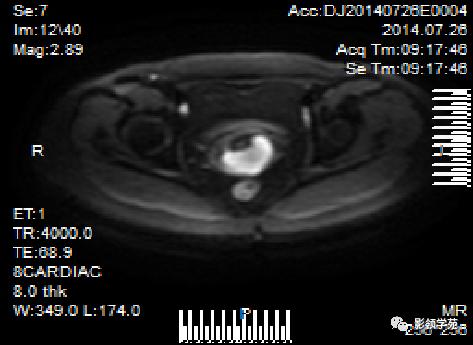

- 新技术:DWI

磁共振扩散加权成像,DWI

DWI是目前唯一能在活体观察组织水分子微观运动的无创性影像学方法,可以检测出与组织含水量变化相关的形态学和生理学早期改变,并以表观扩散系数(ADC)值来量化表示。

DWI:局限性高信号,癌组织ADC值<癌旁组织<小于正常宫颈组织